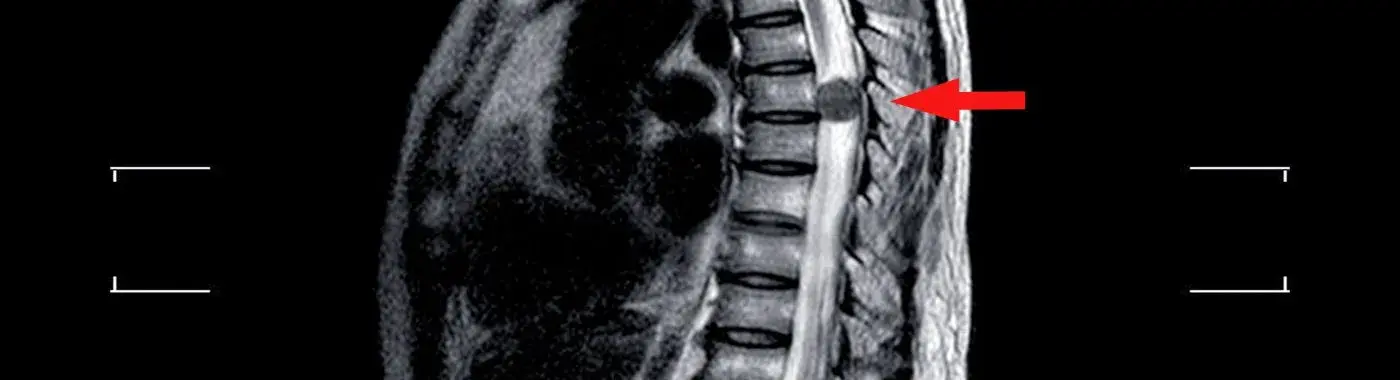

• MRI scan: This is the gold standard for diagnosing extramedullary tumors. An MRI, especially with contrast, shows the tumor's size, exact location, extent of the lesion, and any associated cysts or areas of inflammation.